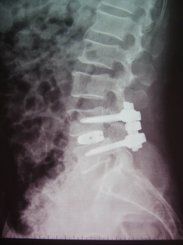

脊柱滑脫通常指某節椎體向前或向後移位,常見於腰椎,在我國腰椎滑脫症是骨科的常見病之一。目前將腰椎滑脫分成發育不良性(包括高度發育不良性及低度發育不良性)、峽部裂性、退變性、創傷性和病理性等6種。其中又以峽部裂性及退變性多見。治療

(7)76%的患者髂嵴連線低於L4-5間盤水平。退行性滑脫一般很少>I度,故多不需復位,手術的目的主要是緩解腰痛和解除神經壓迫,當減壓範圍較大時,可考慮行椎弓根螺釘系統內固定加植骨。

椎弓峽部崩裂性脊椎滑脫手術的主要目的是緩解疼痛和預防滑脫進展。要嚴格掌握手術適應證。近期文獻中就有人報導稱採用椎弓峽部局限固定植骨的方法治療峽部崩裂症,最早為Buck使用螺絲釘貫穿固定加局部植骨,Scott採用鋼絲環繞橫突的棘突固定,國內胥少汀等也報告局部植骨的方法。這些方法在椎弓根螺釘廣泛套用後,已很少被使用。作者對無明顯滑脫的腰痛患者採用椎弓根螺釘加鉤板固定病變椎體的椎弓根和椎板,配合植骨,也取得了較好效果。